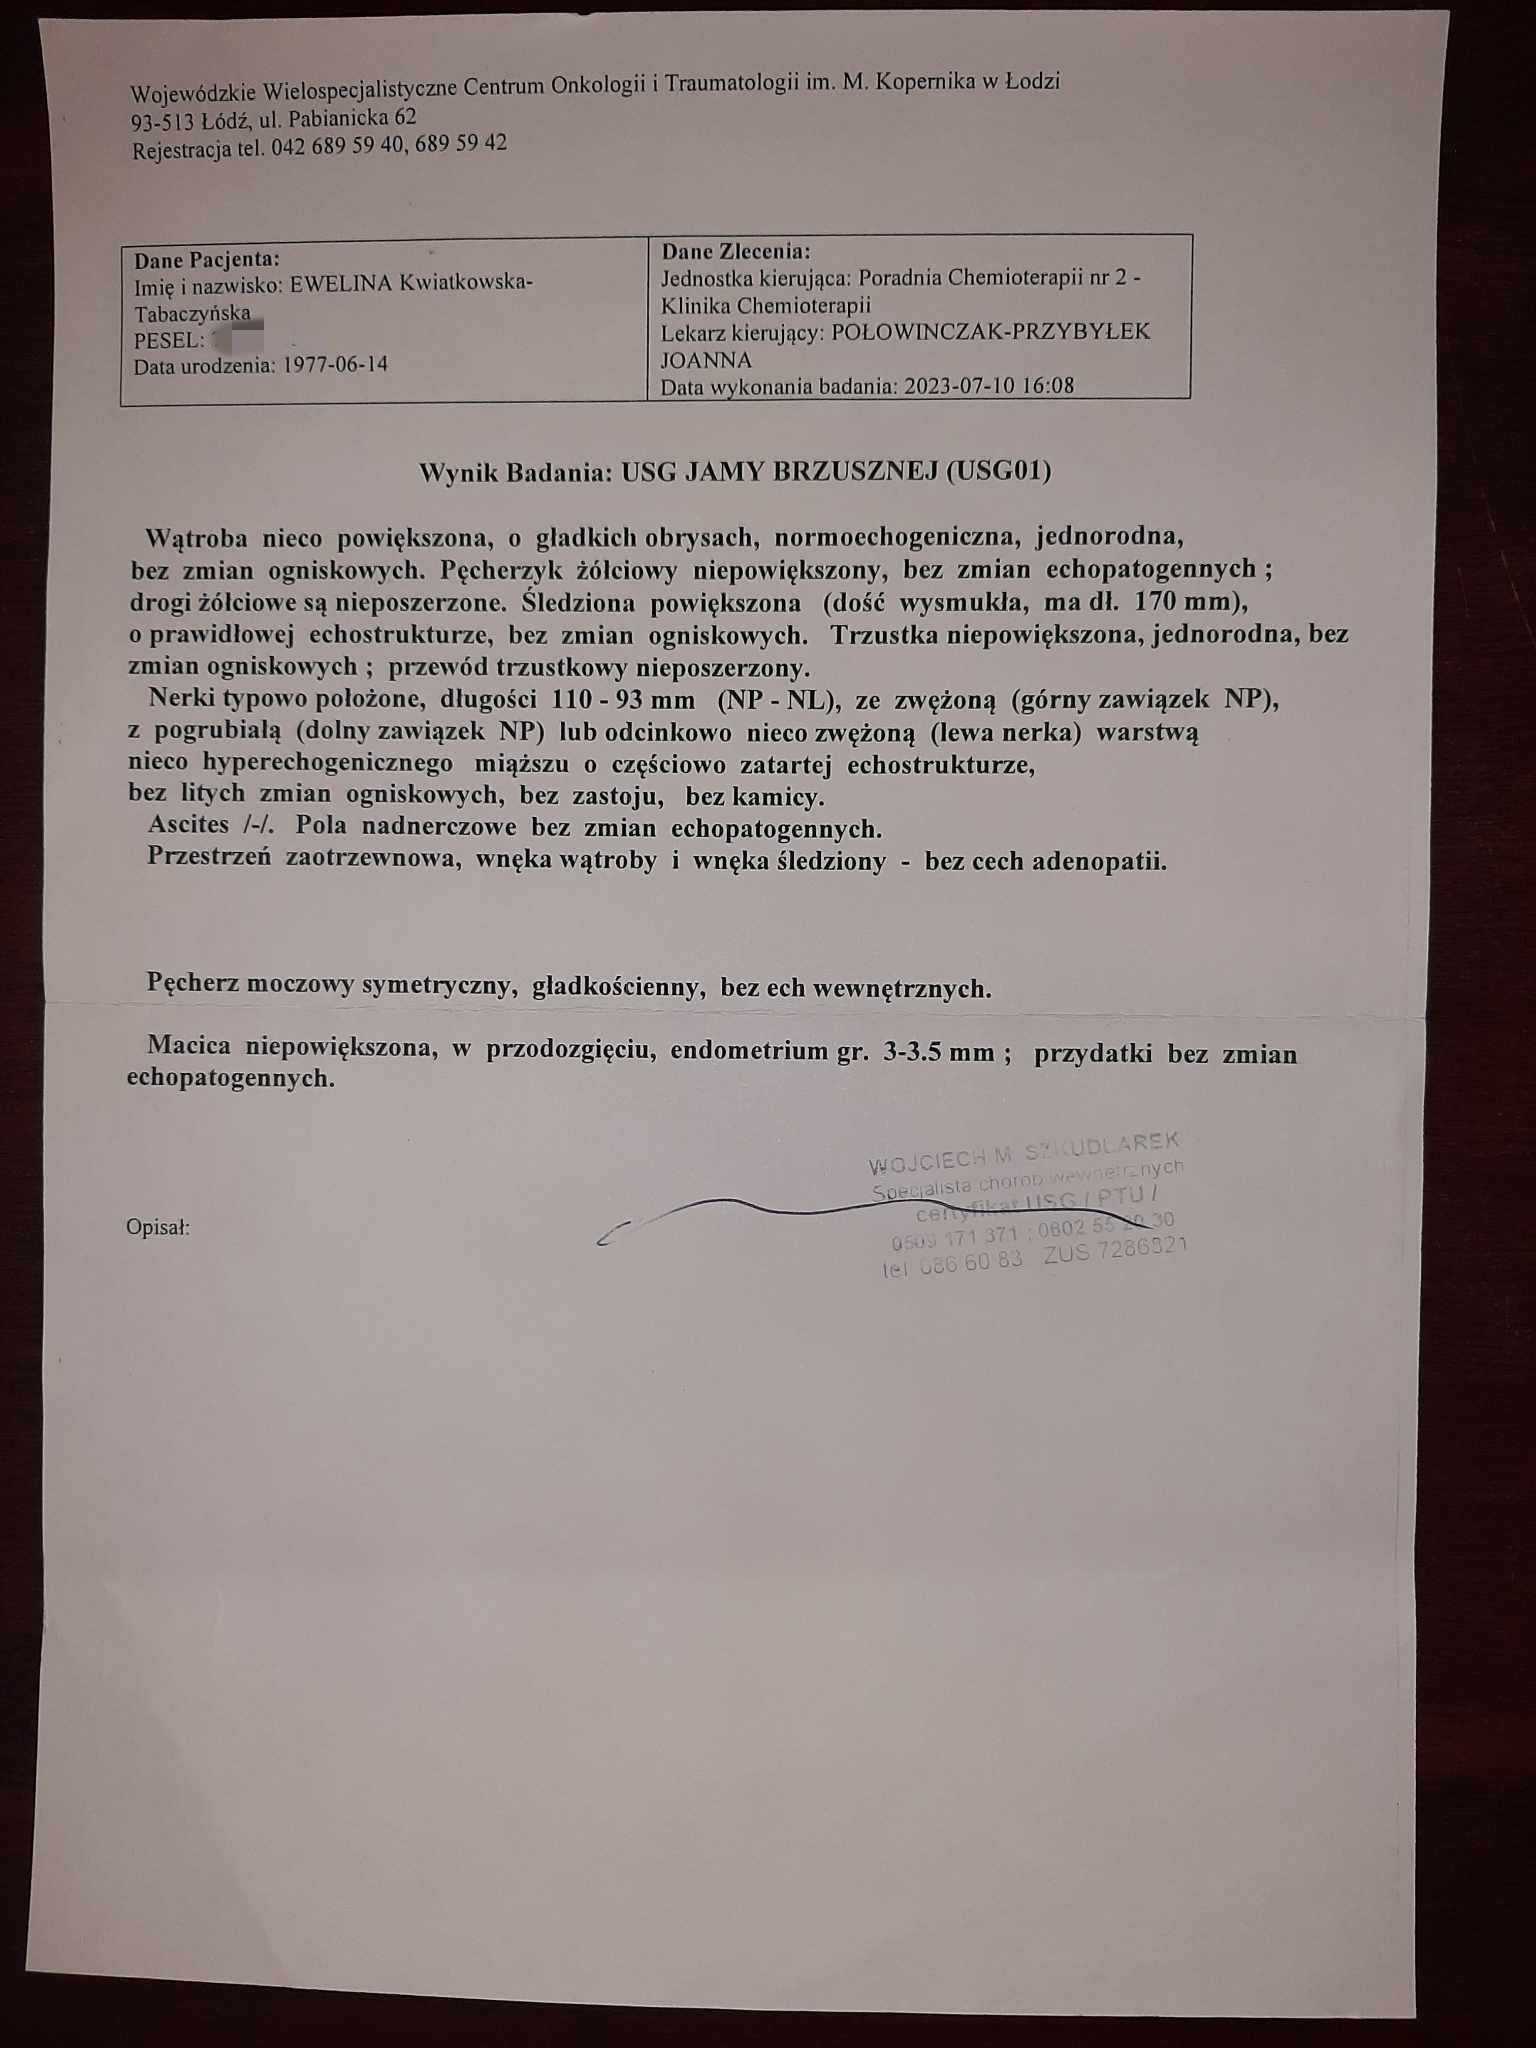

Regularnie co trzy miesiące mam wykonywane wszystkie badania kontrolne w ramach programu lekowego i prowadzonym leczeniem rybocyklibem. Mamy już wyniki usg piersi z dnia 10.07.2023. i wynik usg jamy brzusznej (wyniki poniżej w formie zdjęć), czekamy na wynik scyntografii kości i rtg klatki piersiowej.